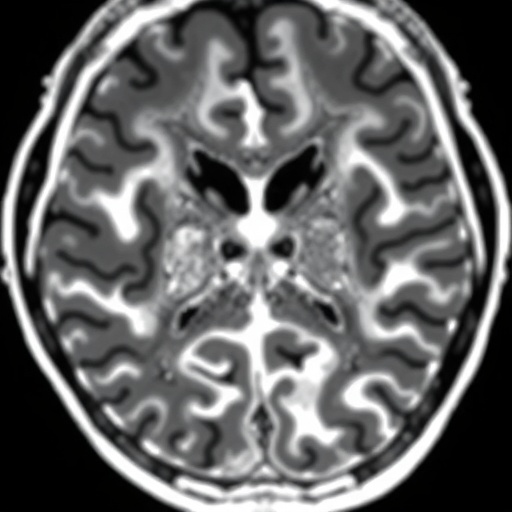

In this extensive research, the authors meticulously examine the reproducibility of grading hindbrain herniation severity through MRI scans. As professionals in the field of pediatric radiology, they recognize the critical need for precise diagnostic tools that can facilitate early interventions and improve clinical decision-making. The study underscores how variations in grading can lead to different interpretations which, in turn, could influence treatment protocols and prognostic assessments. Ensuring consistency in this grading process is foundational to prenatal care, especially as more expectant parents are being informed of potential neural tube defects.

The researchers employed a rigorous methodological framework, analyzing MRI scans of fetuses who underwent prenatal open neural tube defect repair. Each case was meticulously graded, with special attention to the features of hindbrain herniation. By comparing results among different evaluators, the team was able to gauge the inter-rater reliability of the grading system deployed. Importantly, the study emphasizes how discrepancies in interpretations could significantly affect the clinical management of these pregnancies, highlighting the urgent need for standardized protocols in this area.

One of the study’s major highlights is its focus on the role of MRI as a prominent imaging modality in understanding fetal anatomy and potential complications. While ultrasound has been the traditional method for prenatal evaluations, MRI offers enhanced visualization of cranial structures, particularly in complex conditions like open neural tube defects. This allows clinicians to make more informed decisions regarding surgical interventions, ultimately aiming to reduce fetal and neonatal morbidity. The findings herein suggest that MRI not only assists in diagnosis but also plays an instrumental role in pre-surgical planning and subsequent management.